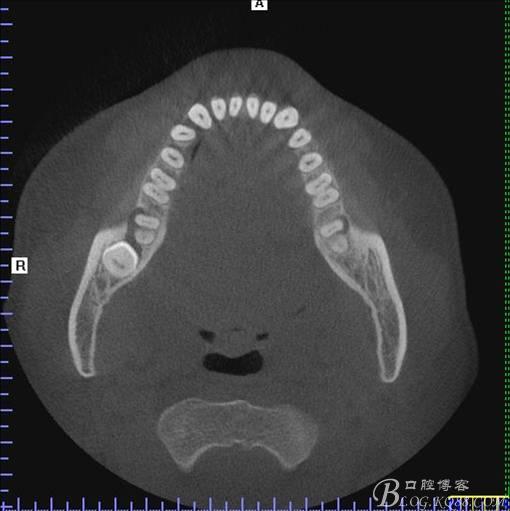

二、術前CBCT影像:

圖4.水平方向48與47之間的關系

圖5. 48的三維視圖